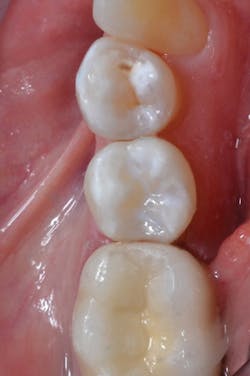

Prime&Bond Elect was generously applied to the entire cavity preparation, and the material was agitated for 20 seconds (figure 3). The excess solvent was removed by gently drying with clean, dry air for at least 5 seconds and light cured for 10 seconds with a dental curing light. The restorative materials were applied to complete the restoration (figure 4).

Figure 3: Prime&Bond Elect was applied to the entire preparation and agitated for 20 seconds.

Figure 4: The completed restoration on No. 29